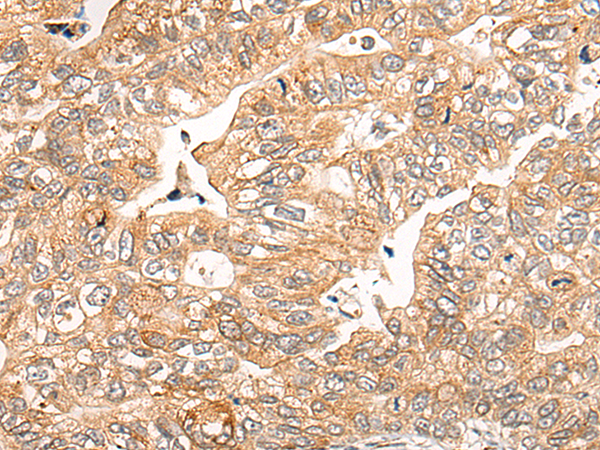

分类: 科研抗体货号: P09471别名:应用: IHC反应种属: Human, Mouse